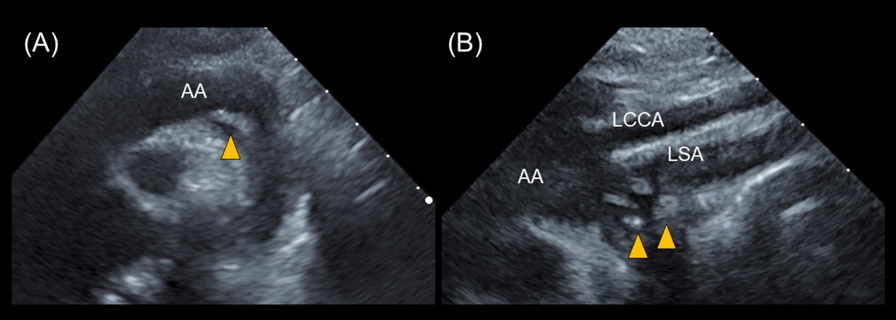

Transthoracic echocardiography revealed multiple vegetations in the aortic arch (Fig. 1). Thoracic contrast-enhanced CT indicated not only SVAS but also stenosis at the origin of either the brachiocephalic artery or the left common carotid artery (Fig. 2). At the time of admission, the patient also experienced left-sided abdominal pain and nausea. Abdominal contrast-enhanced CT revealed renal and splenic infarctions without any arterial aneurysm (Fig. 3). Magnetic resonance imaging (MRI) revealed a very small brain hemorrhage scar. Blood culture detected Abiotrophia defectiva, an endemic oral bacterium that shows penicillin sensitivity. We made a diagnosis of IE according to the modified Duke criteria.4) Urgent surgery for removing vegetations was performed to avoid cerebral embolisms, followed by antibiotic therapy using both penicillin 300,000 U/kg/day and Gentamycin 3 mg/kg/day.

Fig. 3 Abdominal contrast-enhanced CT shows (A) splenic and (B) renal infarction

The arrow heads indicate the areas of infarction.